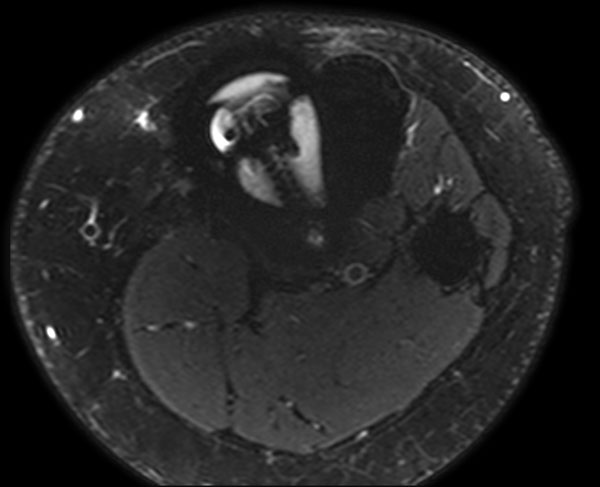

Axial T2w SPAIR